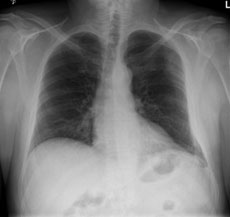

Ein 42-jähriger Freizeitsportler stürzte vor einigen Tagen bei einer Velotour auf die linke Flanke und kommt nun in Ihre Praxis wegen persistierenden thorakalen Schmerzen, v.a. bei tiefer Inspiration.

Sie veranlassen ein Thoraxröntgen, dessen Aufnahmen Sie hier sehen:

Thorax pa

Bild vergrössern